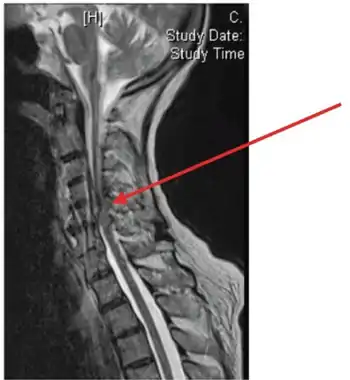

| Image showing epidural abscess (and cord compression) | |

An epidural abscess refers to a collection of pus and infectious material located in the epidural space superficial to the dura mater which surrounds the central nervous system. Due to its location adjacent to brain or spinal cord, epidural abscesses have the potential to cause weakness, pain, and paralysis.